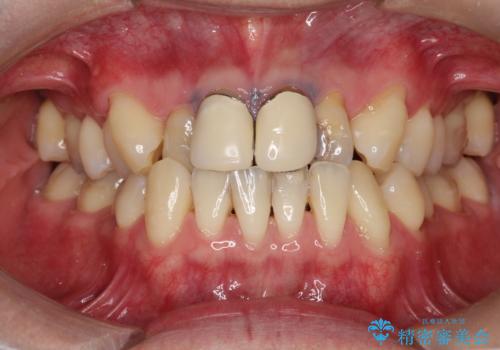

八重歯をインビザラインで非抜歯矯正

- 八重歯を主訴に来院されました。

インビザラインにて奥歯を後方に移動して八重歯が入るスペースを確保してく矯正する計画としました。

八重歯と前歯のガタガタがなくなり、歯並びがきれいになったのと、かみ合わせも改善することができました。